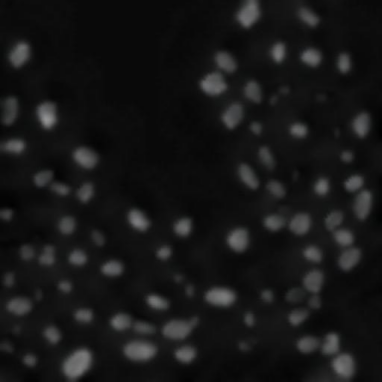

In our pipeline (Algorithm 1, Line 9), we employ AdaIN by using as content the (flattened) generated mask and as reference style a patch from a real image . We train for 30000 epochs using as DA flips and affine transformations for both style and content, and photometric transformations for the style image only. The output of AdaIN is a realistic image where the displayed cells follow the input . Pairs of generated image and mask can be used as annotated samples to augment the small annotated training set . Fig. 4 shows an example of this phase starting from a generated mask and using as reference style an image .

4 Experiments

We validate the effectiveness of our pipeline by training HoVerNet [11], a state-of-the-art instance segmentation NN, on our generated dataset. We start by generating training sets from small subsets of fluorescence microscopy images from the Broad Institute Repository (BBBC) [12]. We then assess the instance segmentation performance on real images from the NucleusSegData dataset [13]. As a baseline, we compare the performance of the same network trained on the full BBBC dataset (Full dataset) and on the few annotated images used for generation (Training real dataset) leveraging standard augmentations. We adopt as metrics those used in HoVerNet, i.e., DICE, DICE2, AJI and AJI+.

During the Blob Placement phase, we model as realizations of Perlin noise [14] as its complex 2D structures resemble a coarse view of the distribution of nuclei in histological images. We estimate the parameters of Perlin noise to maximize the similarity with blurred masks from training data. Then, we perform a preliminary analysis on the distributions of generated GTs to assess how close they are to real ones. In particular, we consider the distributions of area () and aspect ratio (), reporting close results in both the median (: 155px vs. 153px, : vs. ) and in the Inter-Quartile Range (: 32px vs. 39px, : vs. ).

For the image generation phase, we train AdaIN using a tiled version of real images. Then, for each generated mask , we select as reference image the tile having the closest number of blobs to . This choice improves the style transfer procedure, since AdaIN generates images having average value similar to the reference. When the style has too many blobs, artefacts may appear in the image, and when it has too few, the nuclei may be fainter than in real images.

Results shown in Table 1 and in Figure 5 indicate that HoVerNet trained on the full dataset ( annotated images, blobs) achieves an impressive DICE score and AJI score. These values need to be considered as an ideal standard and are displayed with a dashed line in Figure 5. When trained from a generated dataset starting from only two real images ( blobs), HoVerNet achieves DICE score and AJI score, compared to and when the same architecture is trained only on the same two real images. When increasing the number of real images this gap decreases, and the advantages of image generation are lost starting from real images ( blobs). Nonetheless, these results show that our pipeline enables to train models effectively even in very low data regimes.